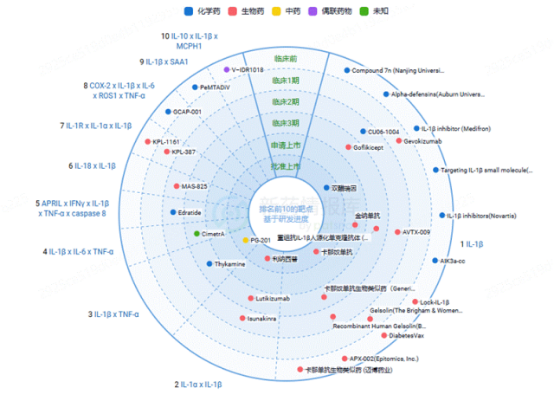

图2. IL-1β药物研发进度